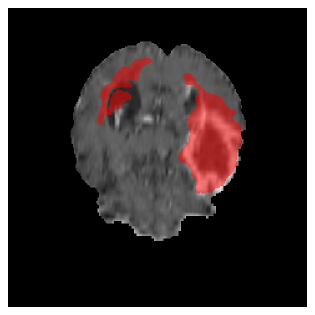

Appendix A Qualitative results

Figure 5 illustrates the segmentation evolution for the same BRATS patient in S2 sequence. The key difference here is that the best buffer-free strategy is EWC (=1), and training on BRATS data starts from episode 2 instead of episode 1 as BRATS is encountered at episode 2 in S2. The cumulative approach retains segmentation across episodes but continues to generate false positives, which become even more pronounced in the final episode. The naive approach, lacking a CL mechanisms, completely overrides previous knowledge, leading to failed segmentation in later episodes. EWC (=1) approach initially maintains segmentation but experiences a sharp decline in episode 4, where it fails to segment the tumor. In the final episode, it undersegments the lesion, missing a significant portion of the tumor. In contrast, the proposed approach consistently preserves segmentation across episodes. While initially introducing false positives, it gradually refines predictions, retaining the tumor region while minimizing misclassifications. It maintains clear tumor delineation by the final episode, demonstrating effective knowledge retention and adaptability throughout training.